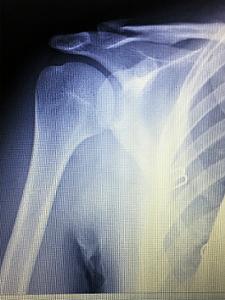

仲が良いのはよいけれど、同じ時期に、しかも同じ右側の肩を・・・

一人は鎖骨骨折、一人は肩鎖関節脱臼を起こしました(笑)。

皆さんは、どっちが骨折で、どっちが脱臼か分かりますか?

正解は、向かって左側が鎖骨骨折、右側が肩鎖関節脱臼でした💛